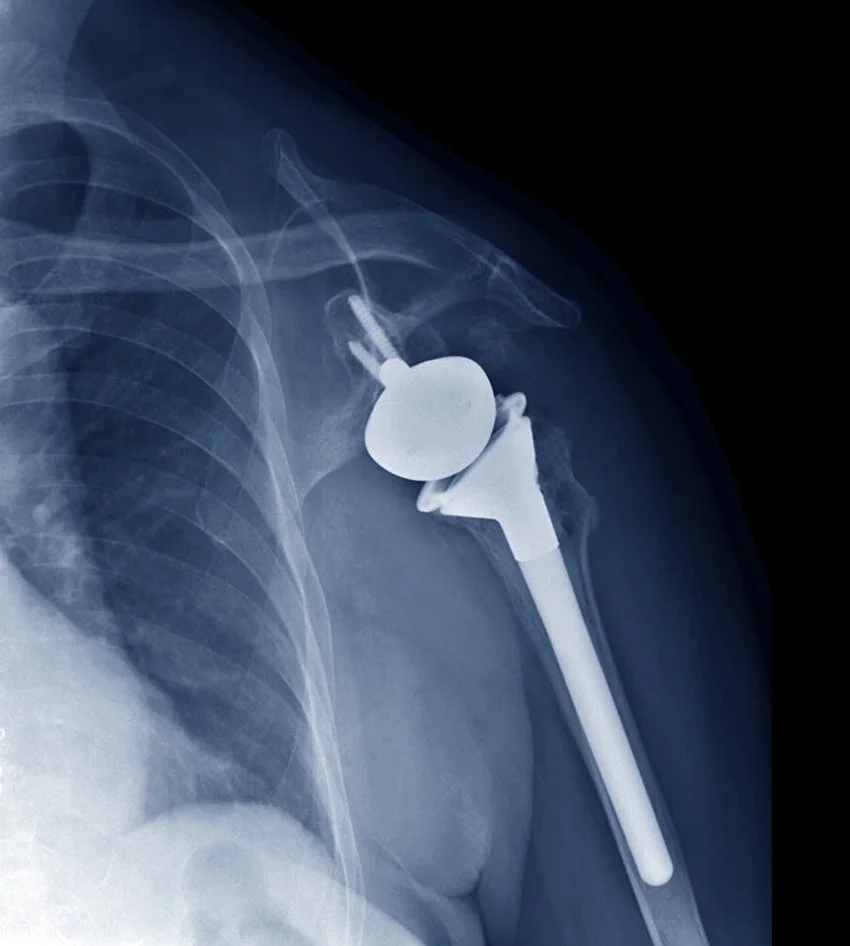

A reverse total shoulder replacement involves removing the worn out ball (humerus) and socket (glenoid) from your shoulder, and replacing them with metallic and plastic components. To help recruit other muscles around the shoulder and give better range of motion and function, we switch the orientation of the ball and socket, so now the ball is on the glenoid side, and the socket is on the humeral side.

• Artificial implants made of cobalt chromium and titanium alloys are positioned to recreate the joint surfaces and restore alignment and function.

• The humeral stem will be inserted into the humerus and the new glenoid will be inserted with a central peg and screws to secure it. These can be either uncemented or cemented depending on your bone quality.

• A glenosphere (ball) is attached to the socket and the humeral component is lined with a plastic to form your new joint